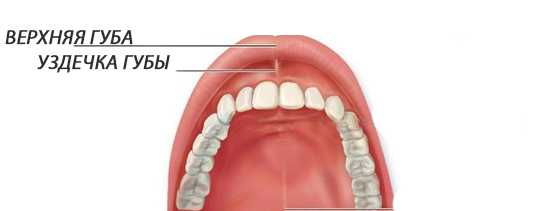

Верхняя губная уздечка—это небольшая складка в полости рта, находящаяся под верхней губой. Она служит для дополнительного прикрепления губы к челюсти.

Пластика уздечки верхней губы у детейЧтобы ее увидеть, следует слегка приподнять верхнюю губу. Уздечка напоминает маленький треугольник, соединенный с десной около резцов.

Нормальное состояние уздечки

Нормой считается, когда она находится на расстоянии 5-10 мм от передних резцов. Уздечка не должна вызывать дискомфорт, мешать речи и приему пищи.

Диагностировать проблему очень просто, нужно лишь приподнять губу, оценить положение полости. Если слизистая складка начинается в середине губы , на 4-6 мм выше десны, ее можно назвать слишком короткой. Такая уздечка может стать причиной развития патологий.